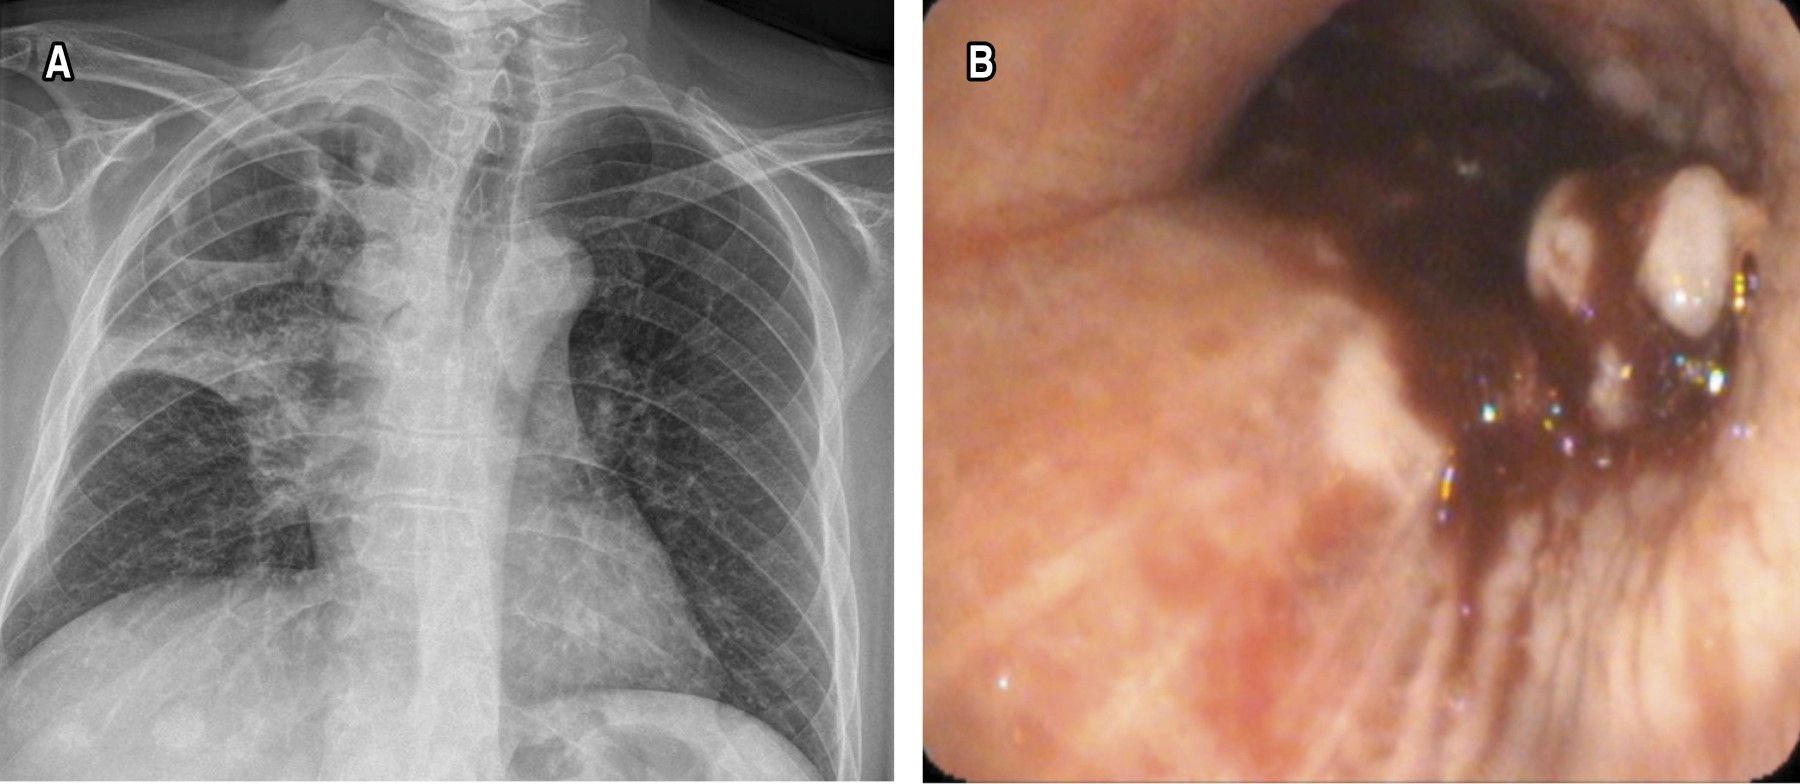

Sixty-four endobronchial tumors were identified, the most frequent location was in the right bronchial tree, with 39 (60.9%) patients. Of these, 19 (29.6%) were found between segments 6 to 10 right, 12 (18.7%) in the middle lobe and eight (12.5%) in segments 1 to 3. In the left bronchial tree, 25 cases (39%) were observed. Of these, six (9.3%) were found between left segments 6 to 10, 10 (15.6%) in the lingula and nine (14%) in segments 1 to 3 (Figures 1 and 2).

Lung cancer remains one of the leading causes of death worldwide, with high mortality rates because most cases are diagnosed in advanced stages. Like other malignant neoplasms, lung cancer can present endobronchial metastasis, complicating its diagnosis and treatment even more. In this context, chest X-rays and CT scans are key tools for the initial identification of lung lesions. In our study, chest radiographs revealed pathological features in most patients, with alterations such as parenchymal opacities, hilar enlargement and pleural effusion, which coincided with reports in the literature, where radiography continues to be useful in the initial detection of neoplastic pathologies.5

Contrast-enhanced computed tomography was also crucial in the evaluation of suspicious lung lesions, providing more precise anatomical details. Tumor lesions were identified in 66.7% of patients and hilar and prebronchial lymphadenopathy was observed in 68.8%, which highlights the importance of this technique in the evaluation prior to more invasive procedures such as bronchoscopy.5